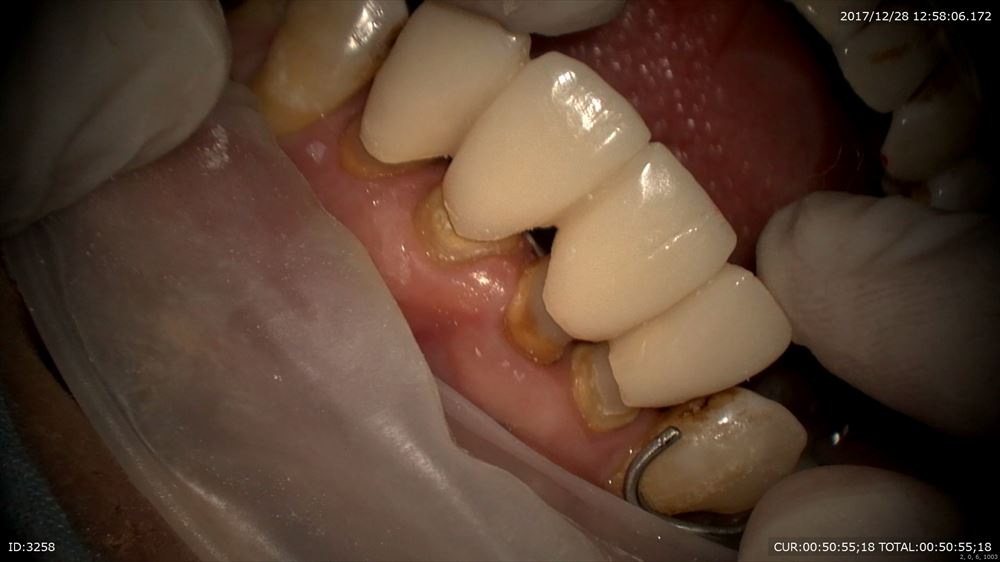

最後は根管治療が終了し土台を作成した方

前歯の根管治療を終了し土台を作成

この状態から

こんな感じ

この土台にも根管内に感染が入らない工夫がしてあります。